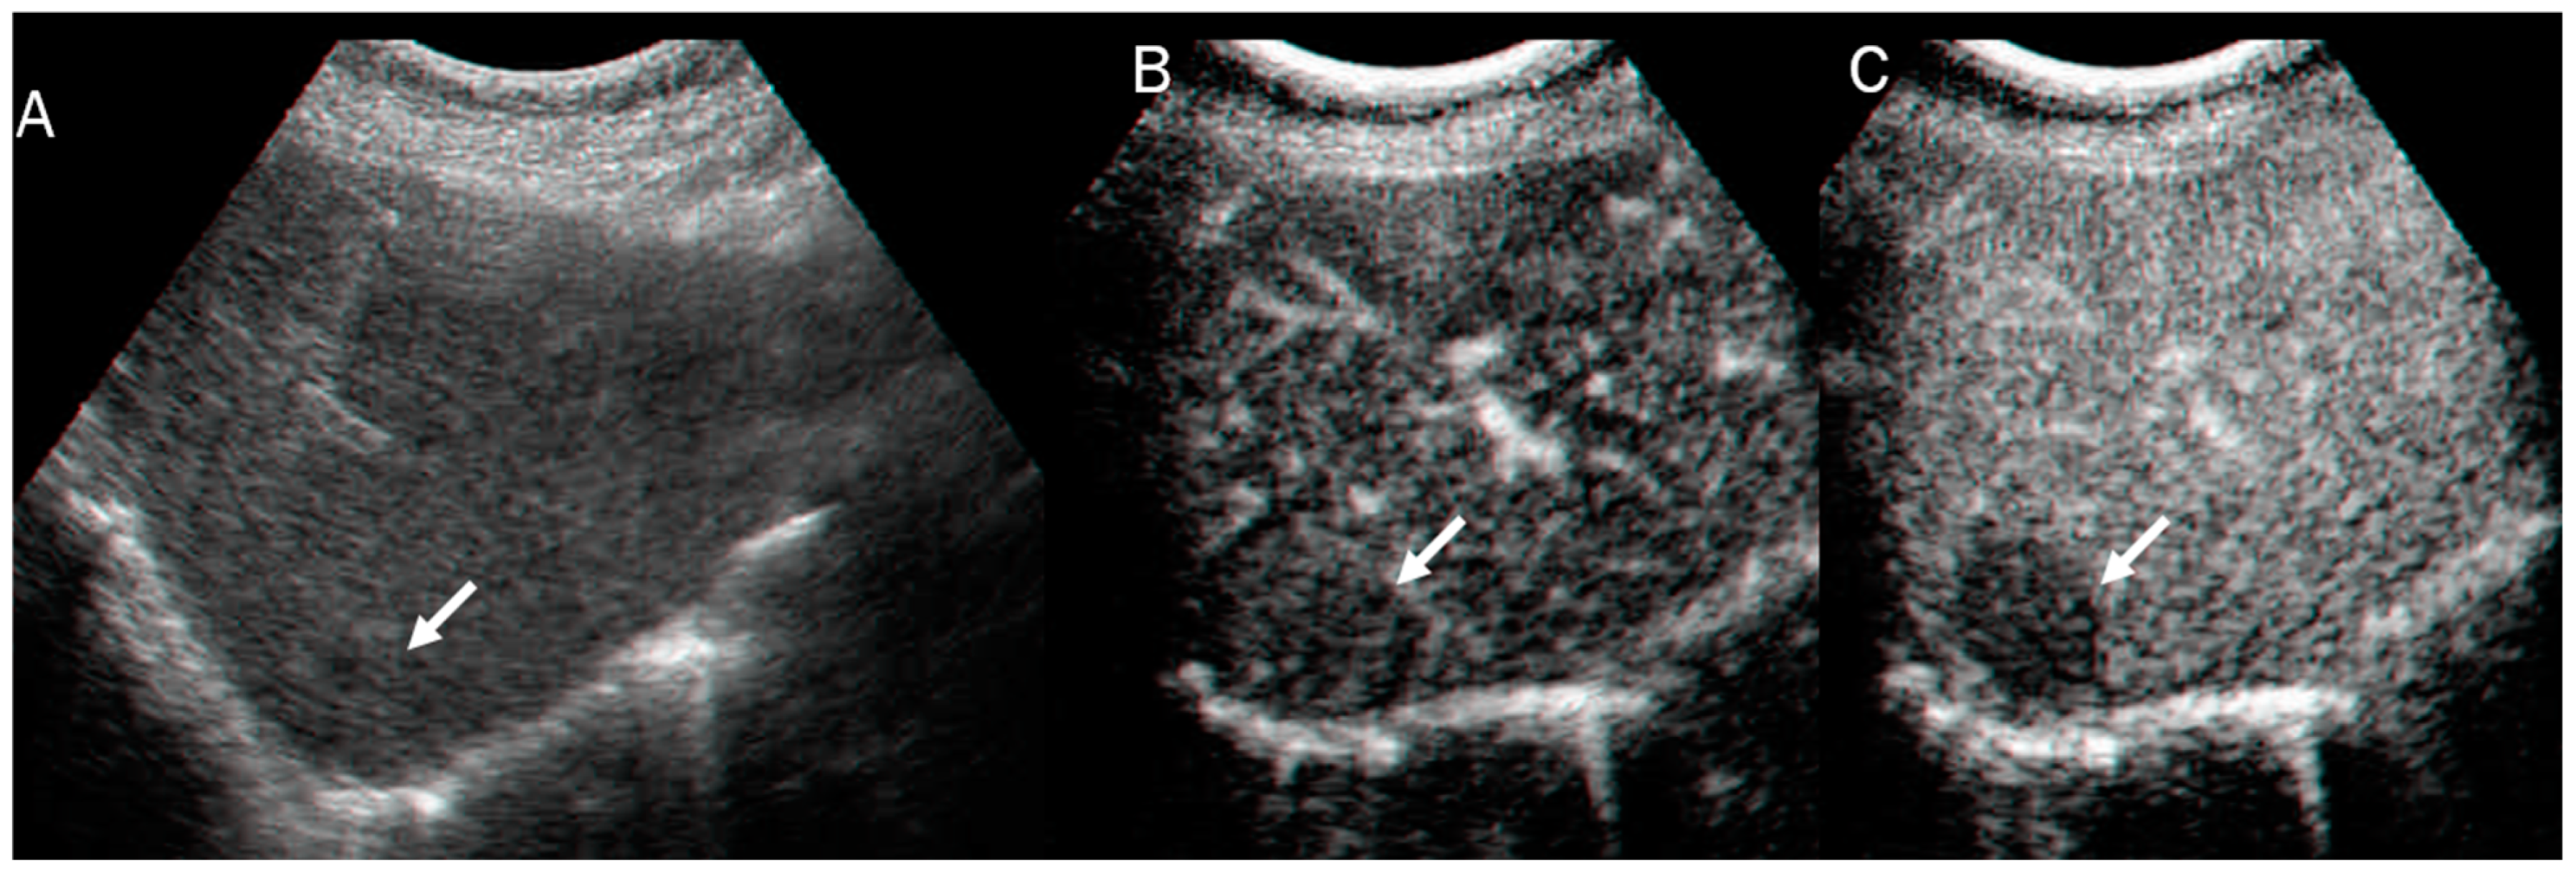

In US studies, mass-forming ICC occurs as a large non-encapsulated mass with lobulated or variable shape. It can also be associated with liver capsule retraction and dilated peripheral bile ducts [80]. With respect to its pathomorphological characteristics (necrosis, fibrosis, and tumor growth), ICC can show a heterogeneous basal-US echogenicity pattern [81]. During CEUS assessment, ICC could show hyperenhancement during the arterial phase (Figure 3) with washout. According to several authors, ICC washout at its earliest stage is comparable to HCC, and this finding should guide a correct diagnosis [82,83,84].

Figure 3.

US and CEUS assessment of ICC: On US (A), the lesion (arrow) shows iso-hypoechoic pattern compared to hepatic parenchymal. During arterial phase (B), the lesion shows arterial hyperenhancement (arrow), with washout (arrow) in portal phase (C).